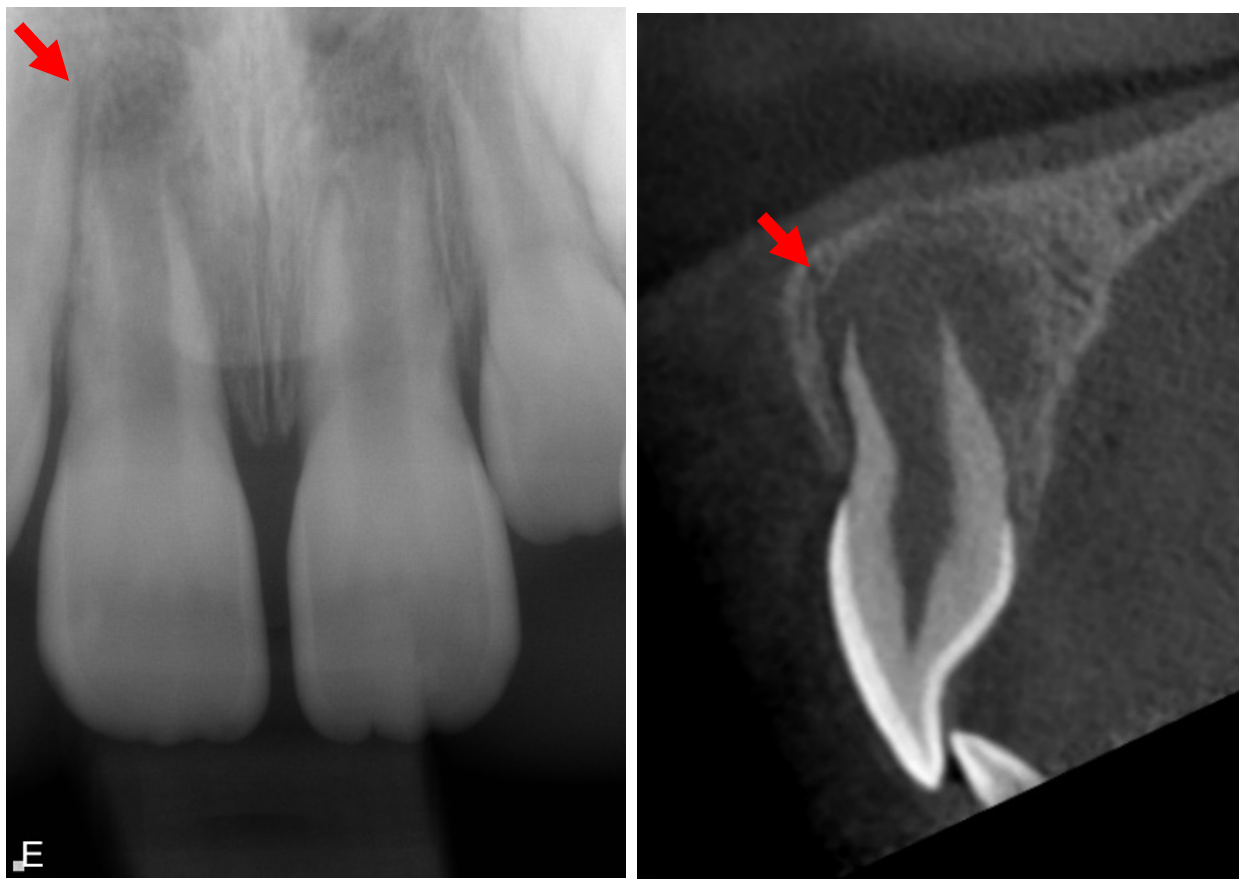

Om unga permanenta tänder går i nekros avstannar rotutvecklingen, och följaktligen har dessa tänder osäker långsiktig överlevnad (figur 1). Ersättning av tänder i ett växande bett kan vara utmanande, och tandförlust kan påverka ungas psykosociala välmående. Att behålla en omogen framtand kan även underlätta eventuellt senare ortodontisk eller protetisk behandling genom att bevara benet eller utrymme tills optimal tidpunkt för extraktion.